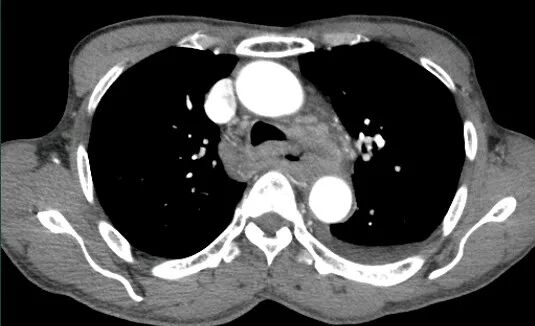

胰腺损伤

在交通意外中,尤其是汽车驾驶人员当汽车高速行驶中,汽车骤然撞于物体上,其强大的惯性使驾驶者的上腹部撞击于汽车方向盘上,导致胰腺受伤。有时当人体自高处坠落,腰部呈过度层曲,同时双侧肋弓极度内收,瞬间一个暴发力,挤压于胰腺上,造成胰腺不同程度的损伤。

胰腺损伤的部位,随外力的方向而异,以胰腺头、体部常见。当外力作用于右上腹或脊柱右侧方,则胰头部易被挤压,同时常合并有十二指肠、胆道、肝脏损伤,此类损伤后果严重,死亡率甚高可达70%~80%;当外力直接作用于上腹中部,则损伤多为胰颈、体部的部分或完全断裂,并合并有肠系膜上动脉损伤;外力作用于脊柱左侧方,胰尾常易受伤,此时多伴有脾破裂。